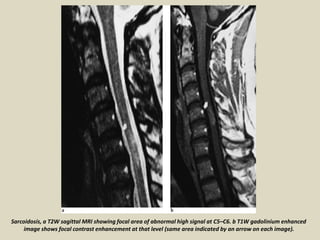

Sarcoidosis, a T2W sagittal MRI showing focal area of abnormal high signal at C5–C6. b T1W gadolinium enhanced

image shows focal contrast enhancement at that level (same area indicated by an arrow on each image).